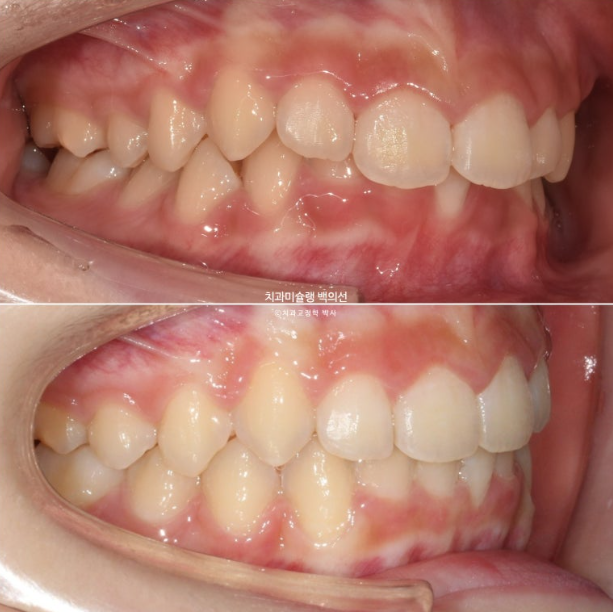

25.04

중심선은 정확하게 맞으며 과개교합이 잘 해소되었습니다.

어금니 교합은 물샐틈 없는 1급입니다.

2024.02~2025.04

유지장치까지 들어간 모습입니다.

총 치료기간은 1년 2개월, 재제작은 1회 했습니다.